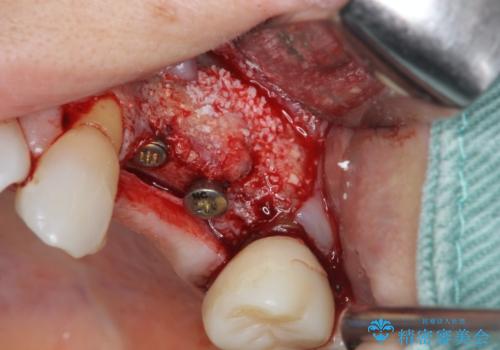

抜去後の補綴治療は長いブリッジではなくインプラント治療を希望されましたが、穿孔・破折による周囲の骨吸収をリカバリーすべく骨の造成を伴うインプラント治療を計画します。

インプラント治療を行うにはインプラント周囲に十分な骨の幅・高さが必要です。

今回はが原因で失われてしまった骨の幅を回復することで長期的な予後を見込めるインプラント治療を行うことができました。